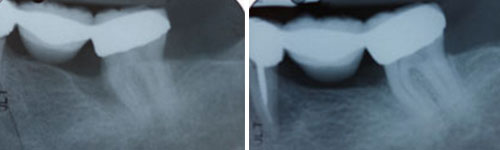

In a healthy mouth, the teeth are firmly surrounded by gum tissue and securely supported by the bones of the jaw. Periodontal disease damages these tissues and bones, leaving open spaces around the teeth that we call pockets. The larger these pockets are, the easier it is for bacteria to collect inside them, leading to more and more damage over time. Eventually, the supportive structure degrades to the point that the tooth either falls out or needs to be removed.During pocket reduction procedures (also known as “flap surgery”), we fold back the gum tissue and remove the bacteria hiding underneath, as well as the hardened plaque and tartar that have collected. We may also remove any tissue that is too damaged to survive. We then sew the healthy tissue back into place. Now that the tooth and root are free of bacteria, plaque and tartar, and the pockets have been reduced, the gums can reattach to the teeth.